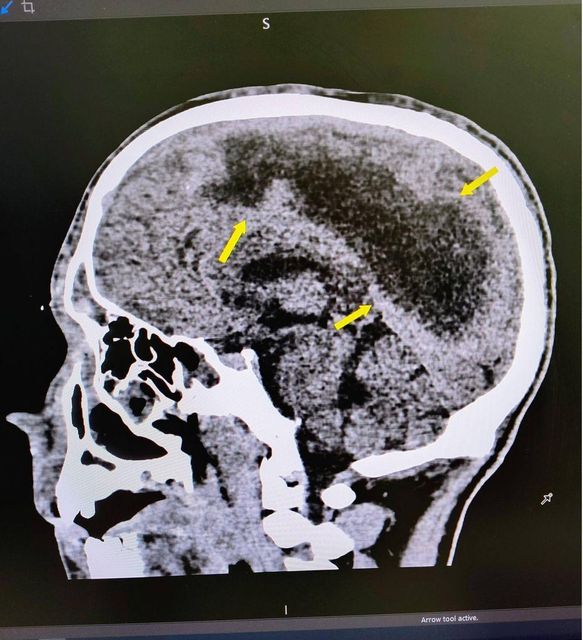

— Пацієнтові, який потрапив до нас у стані коми, провели комп’ютерну томографію і виявили масивне скупчення гною у правій півкулі головного мозку. Емпієма могла призвести до розвитку сепсису (інфекція потрапляє у кров і поширюється по всьому організму), порушення серцевого ритму чи зупинки дихання.. Тож під час операції нейрохірурги дренували гнійник, який, на щастя, не призвів до ушкодження життєво важливих центрів.

Окрім того, КТ показала, що приносові пазухи пацієнта — запалені (йшлося про двобічний гайморит і двобічний фронтит). Тож наступного дня лікарі провели пункцію гайморових пазух, видаливши звідти гнійний вміст. Праве око юнака випирало — гній потрапив у його внутрішні тканини, відтак розвинулась флегмона орбіти. Це загрожувало ушкодженням зорового нерва й втратою зору. Тож під час тривалої операції спершу команда отоларингологів методом трепанації видалила гнійний вміст з фронтальних пазух. А потім окулісти здренували флегмону орбіти й надалі тривалий час промивали пазухи для повного їх очищення, проводили антибіотикотерапію.

Загалом же протягом трьох тижнів пацієнт був у комі, два тижні — під апаратом штучної вентиляції легень. Коли Олексій прийшов до тями, в нього був парез (слабкість) лівої частини тіла, тож з ним працювали реабілітологи — вчили заново ходити. Зрештою стан пацієнта повністю відновився, недавно він проходив контрольне КТ — все добре.